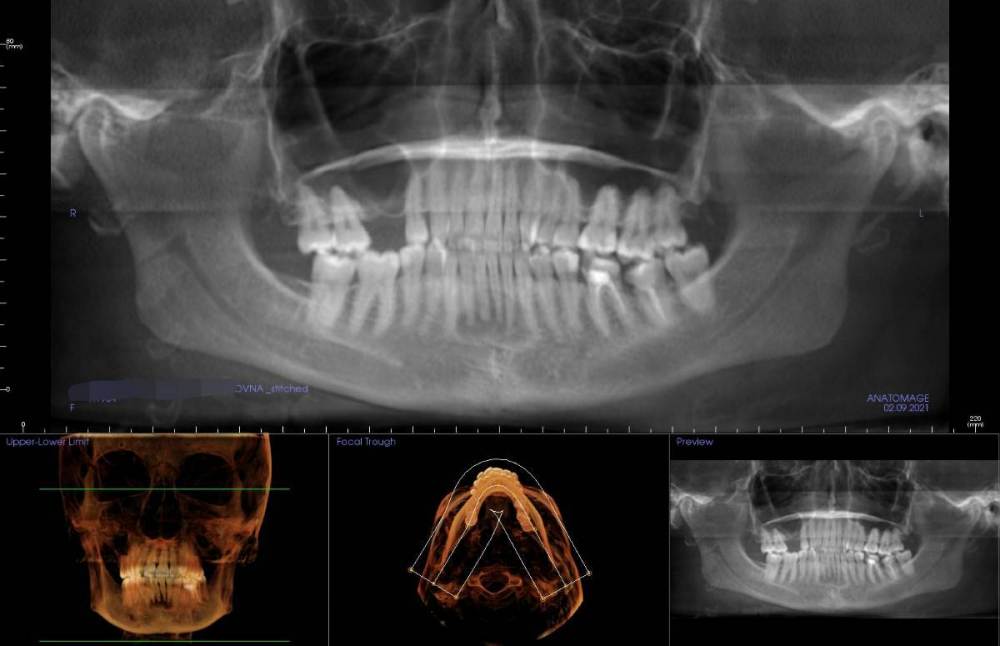

Ситуация в следующем: у меня стоят брекеты, пока только на верхней челюсти, ношу ~8 мес. На нижней челюсти в переднем отделе обнаружена цементно-костная дисплазия. Делалось два КТ, первое в 2021 (перед установкой верхней челюсти), второе месяц назад для оценки динамики перед установкой брекетов на низ. Дисплазия стала немного больше, но выглядит лучше (больше костной ткани).

Вопрос: можно ли ставить брекеты на нижнюю челюсть при таком диагнозе? Какие есть риски, осложнения? На фото КТ, сделанное в 2021